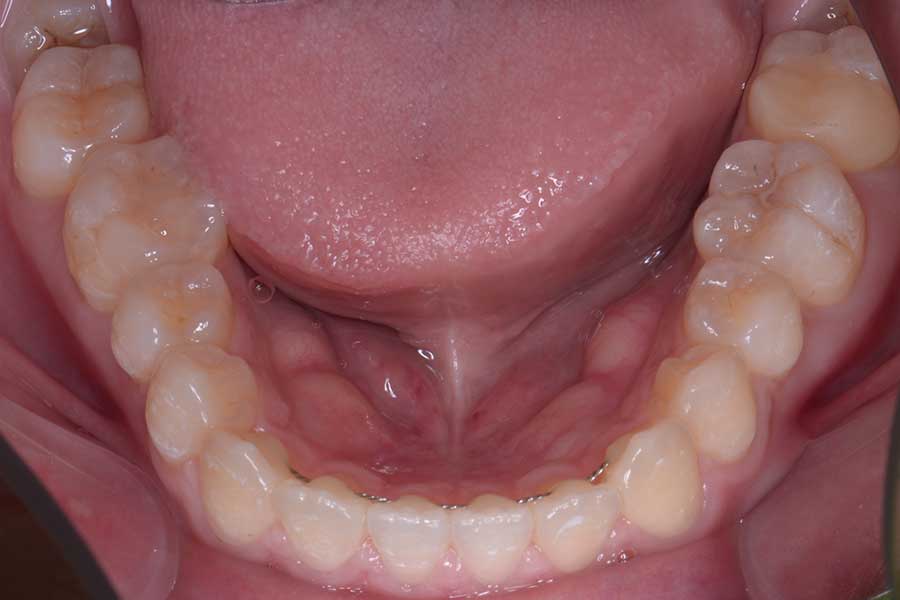

【20代女性】捻じれと段差と咬み合わせを治したい

• 治療前

主訴 捻じれと段差と咬み合わせを治したい

治療内容 上下顎ラビアル矯正(表側矯正)